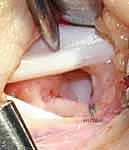

الخطوة 2: الشق الجراحي التجميلي

يقوم الدكتور هطيف بعمل شق جراحي دقيق ومدروس، غالباً ما يكون متماشياً مع خطوط تجاعيد الجلد الطبيعية في المعصم (Langer's lines) لضمان أن تكون الندبة المستقبلية شبه غير مرئية.

الخطوة 4: الإغلاق التجميلي

يتم إغلاق الجرح بخيوط تجميلية دقيقة جداً، ووضع ضمادة ضاغطة خفيفة لدعم المعصم وتقليل التورم بعد العملية.